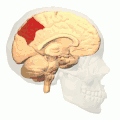

![]() Sagittal MRI slice with the precuneus shown in red. (Anterior to the left.) | |

In neuroanatomy, the precuneus is the portion of the superior parietal lobule on the medial surface of each brain hemisphere. It is located in front of the cuneus (the upper portion of the occipital lobe). The precuneus is bounded in front by the marginal branch of the cingulate sulcus, at the rear by the parieto-occipital sulcus, and underneath by the subparietal sulcus. It is involved with episodic memory, visuospatial processing, reflections upon self, and aspects of consciousness.